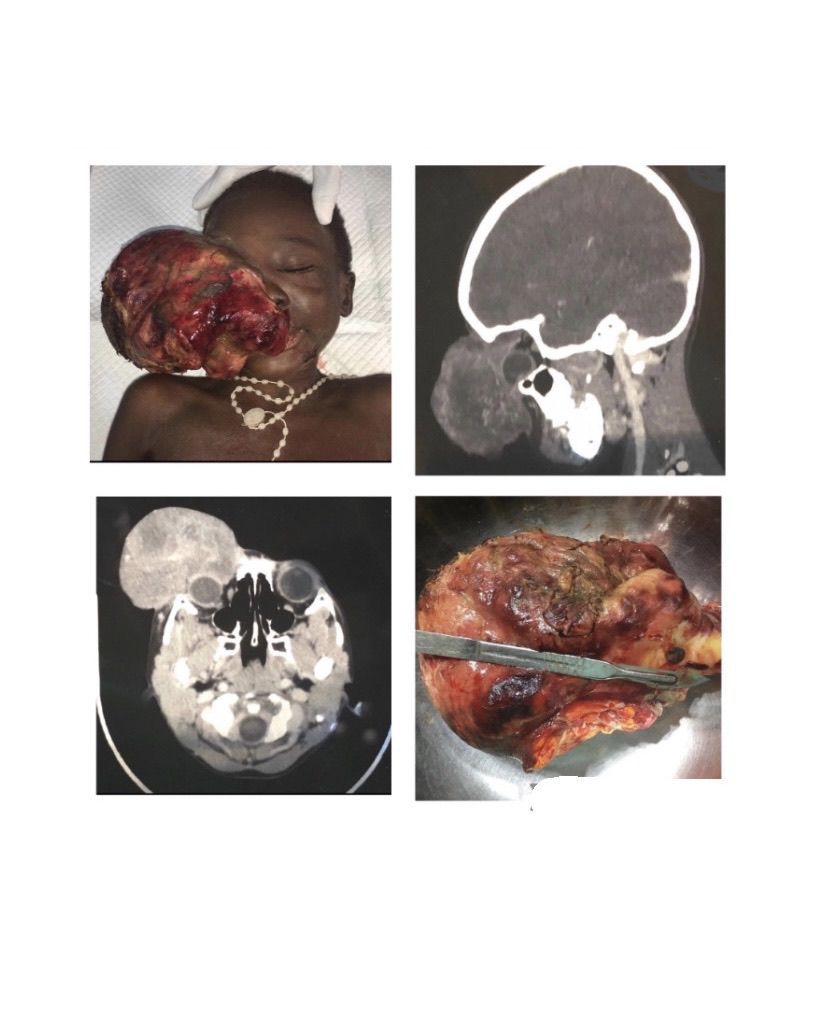

Retinoblastoma is a rare cancer of eye that develops from multipotential precursor cells. This malignancy develops in childhood and involves mutation of Chromosome 13 band 13q14. Signs and symptoms includes leucocoria, vision deterioration, glaucoma, strabismus, redness, swelling and even blindness. Treatment option includes chemotherapy, radiotherapy, cryotherapy, thermotherapy and surgical interventions. Picture credit: @earthwidesurgicalfoundation (via Instagram)